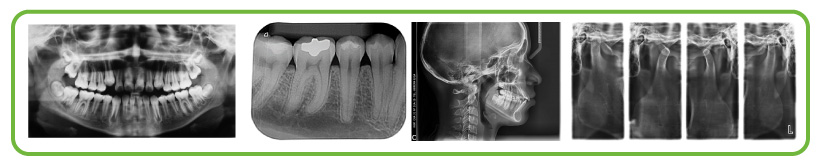

Sistema que nos permite tener tomas radiográfico en fracciones de segundo, con imágenes nítidas que nos ayudan a llegar a diagnósticos con mayor precisión. Permite la generación de un archivo por paciente pudiendo mejorar la comunicación con el paciente y con otros profesionales para decisiones prontas y oportunas.

- Periapical

- Panorámica

- Lateral

- ATM